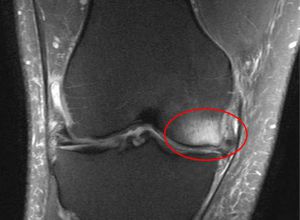

Susquehanna Orthopaedics has partnered with Conformis to offer you the latest in knee replacement technology. These customized implants are created to meet the precise size and shape of a patient’s knees.

Our partner, Conformis, wanted to address this issue by developing knee implants for every one of our patients. Their aim for this groundbreaking technology is to give you a pain-free lifestyle by helping you recover your natural motion so you can return to your regular activities. These custom-made knee implants are built distinctly for your particular anatomy, providing the best results in knee replacement surgery.